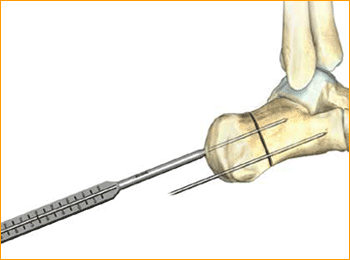

9. SCREW INSERTION

Cannulated Screws are placed. Placement is confirmed by lateral and axial fluoroscopy views in the operating room.

Caution: The marking on the driver shows when the screw is approximately flush with the end of the soft tissue protector; assure that the soft tissue protector is touching bone to accurately determine screw depth. Verify final screw position with fluoroscopy.

10. ADDITIONAL SCREW PLACEMENT

Repeat steps 5–9 for each additional screw placement. The operative limb is placed into a bulky compression dressing. A splint is also placed. Patients are made non-weight-bearing in a cast, boot, or splint for 6 weeks after surgery.